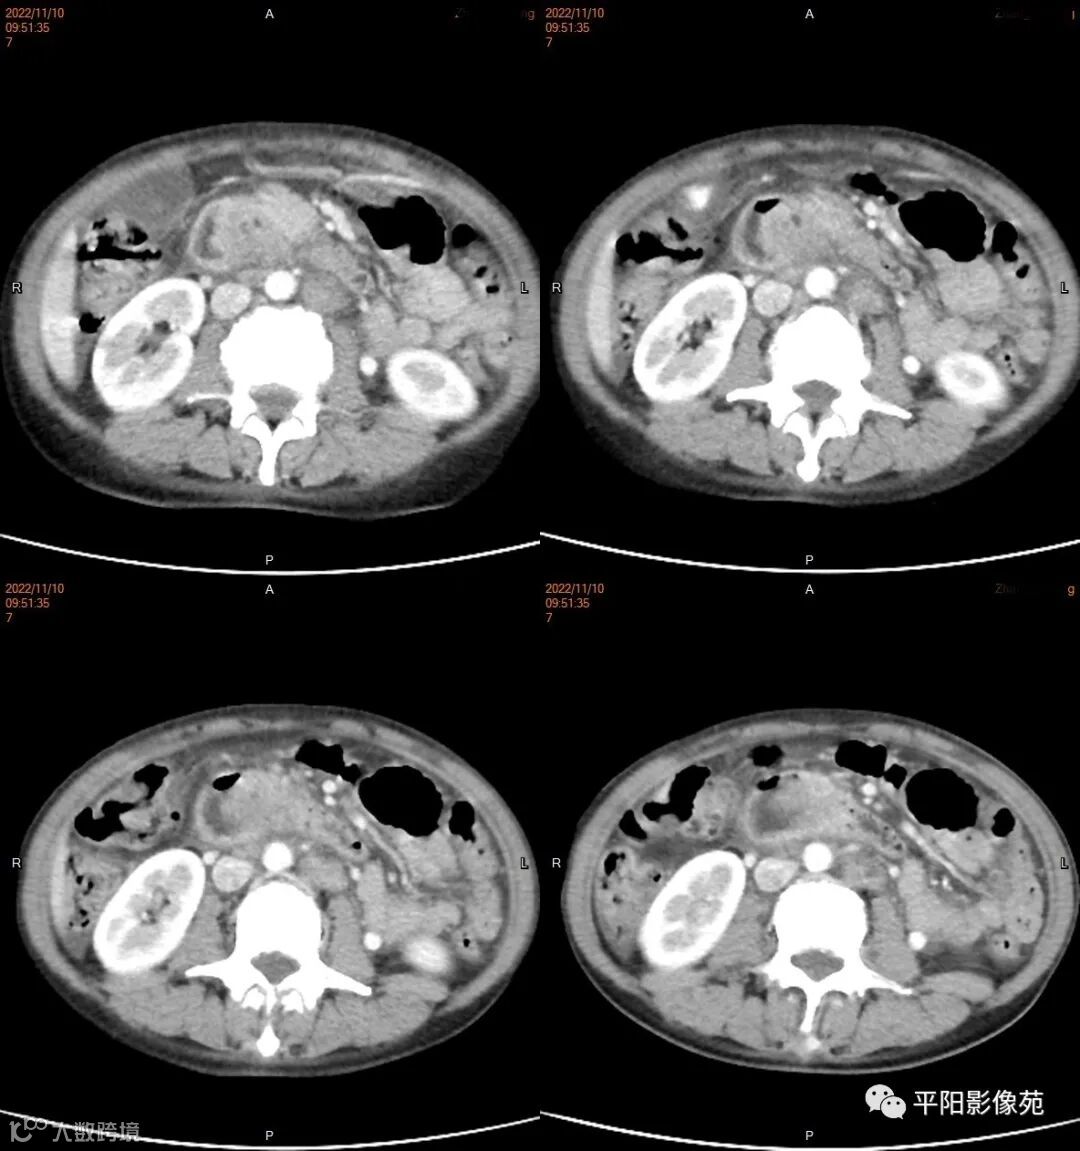

影像学检查

CT

影像表现: